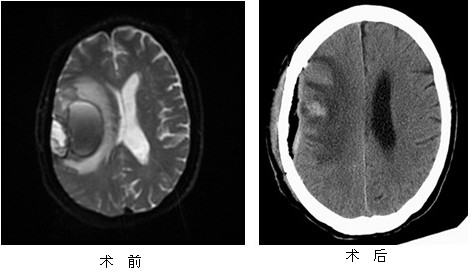

针对患者的病情,神经外科组织了全科讨论,认为该患者病情极为严重,因病情复杂,当务之急是控制脑出血并抓紧时机查清病因。遂急行脑核磁共振检查:提示右侧额顶颞叶占位病变,考虑脑肿瘤卒中。且肿瘤位于中央脑功能区中央前回附近,手术难度大,术后极易使偏瘫等神经系统症状加重,这无疑对神经外科医生来说是一巨大挑战。神经外科经过讨论,对手术进行了周密设计,决定采用显微手术的方法切除肿瘤并同时清除血肿。1月7日,在全麻下为患者施行右额颞颅内肿瘤切除+血肿清除术,手术中张洪兵主任医师、曹文军副主任医师等经过3个小时的努力,应用显微操作技术全部切除了肿瘤,最大限度地保护了功能区脑组织,彻底止血,手术顺利。术后患者未出现瘫痪等并发症,手术效果良好。病人肢体活动、语言功能及意识情况恢复良好,生活基本自理,于近日顺利出院。

脑肿瘤卒中在临床上发病率较低,而以首发脑出血就诊的脑肿瘤卒中病人更少。这类患者病情复杂且危重,临床上极易误诊,风险极高,应尽早明确诊断予以切除肿瘤,清除血肿,挽救病人的生命。此例手术我院尚属首次开展,在北京市二级医院及部分三级医院也属先进水平,手术既清除了血肿同时又切除了肿瘤,在挽救病人生命的同时又改善了患者的生活质量。